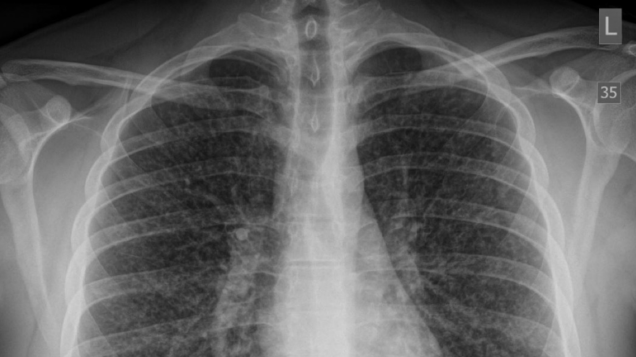

A Canadian teenager developed a life-threatening condition known as “popcorn lung” after several months of intense vaping, in the first medical case linking this chronic lung disease to e-cigarette use.

Source: Gizmodo – Doctors Report First Documented Case of ‘Popcorn Lung’ From Vaping